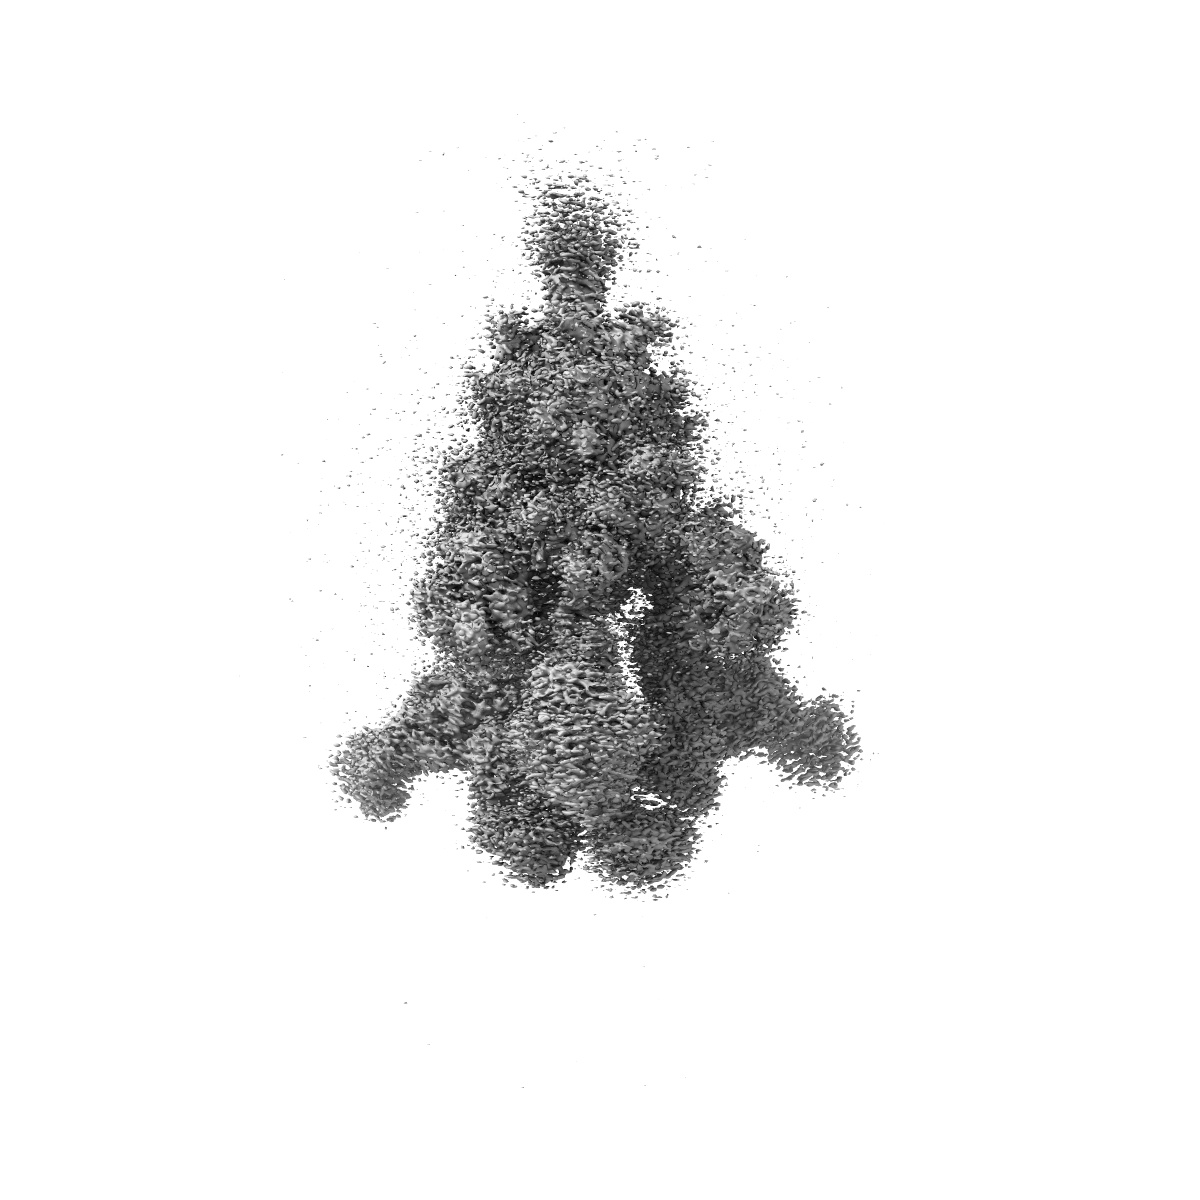

Cryo-EM structure of SARS-CoV-2 Omicron BA.4 S-trimer in complex with fab L4.65 and L5.34

Single-particle

2.85 Å